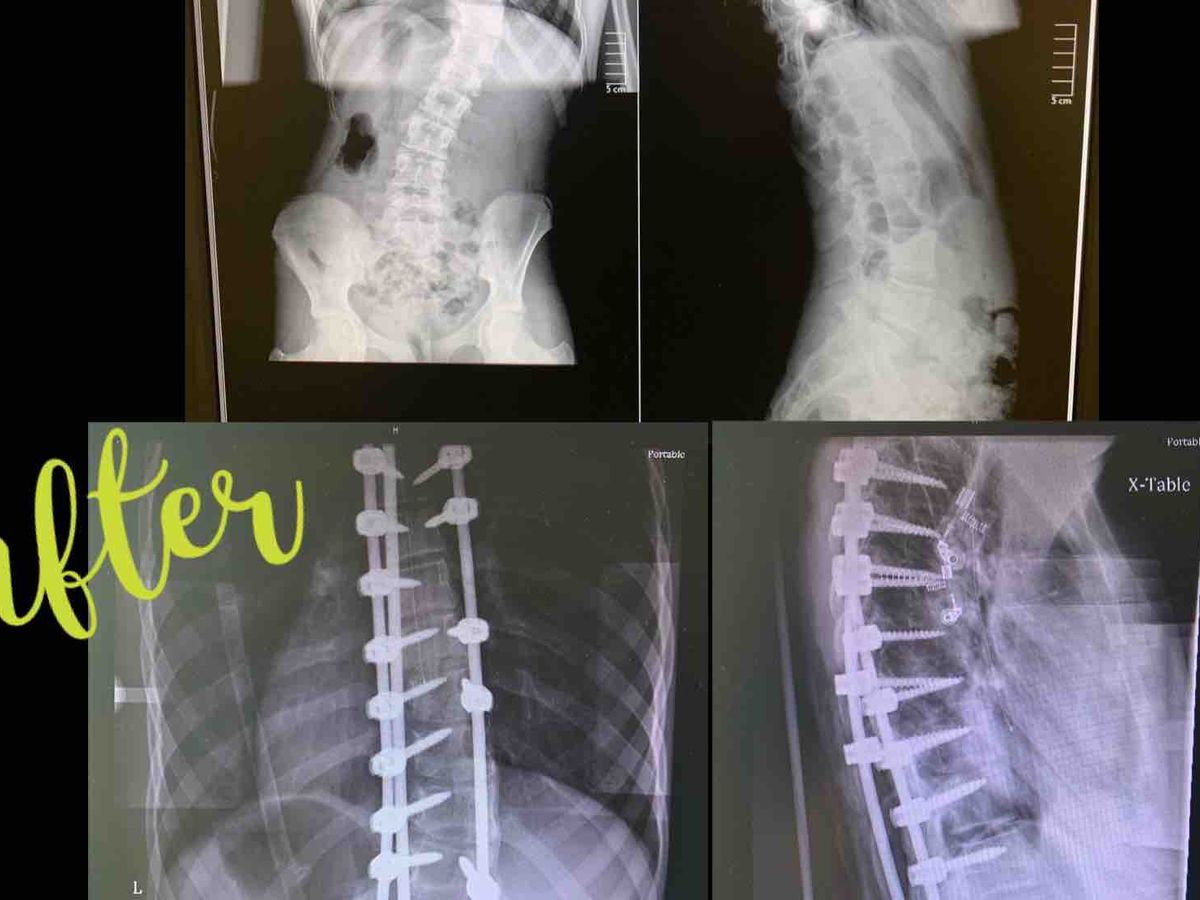

Here we are, just a year after we found out Justice has Scoliosis. We tried chiropractic care but her curvature has increased over 10 degrees in the last year and her specialist said it isn't going to stop. She is past the point for wearing a brace too. She is in pain all the time. Sometimes with a smile on her face and doing things the other kids are doing because she doesn't want to miss out. But still in pain. We have decided to proceed with back surgery. She has decided she wants to do this. It's major. It's a long recovery. She has done her homework on it, most would be scared to even know what this surgery entails. The specialist said her spine is flexible, which is great, that will allow him the best chance to get her as straight as possible.

The surgery is over 5 hours long, with a 3 day stay in the hospital and 6 weeks at home for recovery, so she will not be able to go back to school this semester. Then it's a 6 month recovery for her spine to heel. There will be good days and for sure some bad ones.